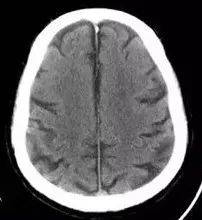

放射冠半卵圆中心

半卵圆中心与放射冠

半卵圆中心与放射冠有什么区别

放射冠与半卵圆中心的区别

放射冠(白质) 沟回 半卵圆中心

额叶 放射冠 顶叶

半卵圆中心

放射冠

【解剖学习】放射冠区的解剖图----看后你可会定位?

半卵圆中心放射冠分不清

3-半卵圆区